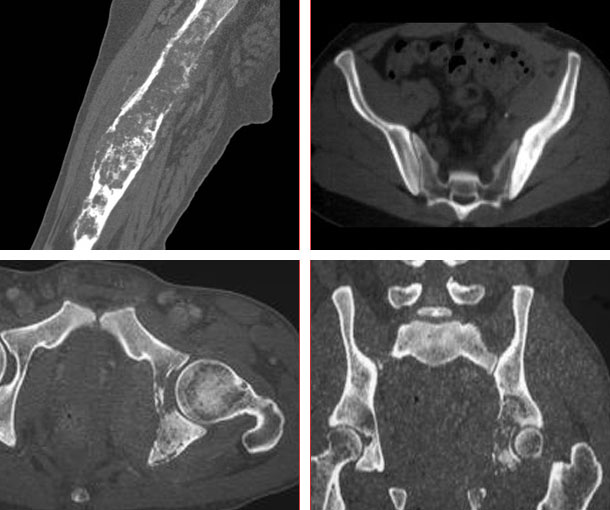

Lymphoma of Bone CT Findings

- Typically involves the long bones

- Long bone with a solitary, well defined lytic lesion at the end

- “Moth eaten” destruction

- Multiple small rarefactions parallel to long axis of bone (permeative destruction)

- Aggressive periosteal reaction

- Extra-osseous soft tissue mass

- Cortical breakthrough may be present in more advanced cases

- May have lymph node involvement

- CT findings are not specific for primary lymphoma of bone